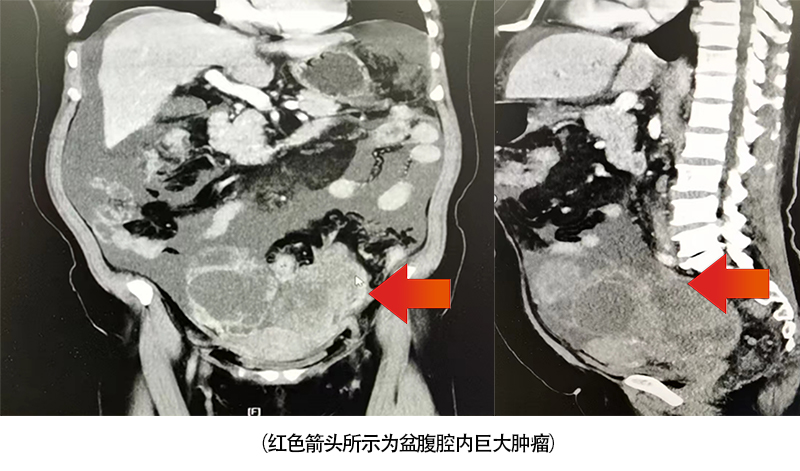

据介绍,患者何阿姨今年52岁,因“腹胀”于外院就诊,外院诊断为晚期卵巢癌,肿瘤已多处转移,手术难度大,建议转诊。2023年1月25日,患者慕名前往中南大学湘雅三医院就诊,就诊时患者主诉因腹腔内大量腹水,稍活动后便感明显气促,夜间已不能平卧入睡,遂接受入院治疗。入院经检查发现患者肿瘤标志物CA125高达5857U/ml(正常人该项指标一般小于35U/ml),双下肢B超提示下肢血栓形成。CT提示盆腹腔内巨大肿瘤(肿瘤最大径接近20cm),同时肿瘤已侵犯肠道、大网膜及淋巴结。医院妇科邓新粮主任医师、肝胆胰Ⅱ科聂晚频主任医师、胃肠外科Ⅰ科周剑宇副主任医师、血管外科刘炼副主任医师、泌尿外科彭冬毅医师、麻醉科段开明副主任医师等在内的妇科肿瘤MDT团队进行第一次讨论后,考虑患者晚期卵巢癌合并深静脉血栓,一般情况差,不具备手术条件,遂分别于1月31日、2月20日给与患者2个疗程的化疗。